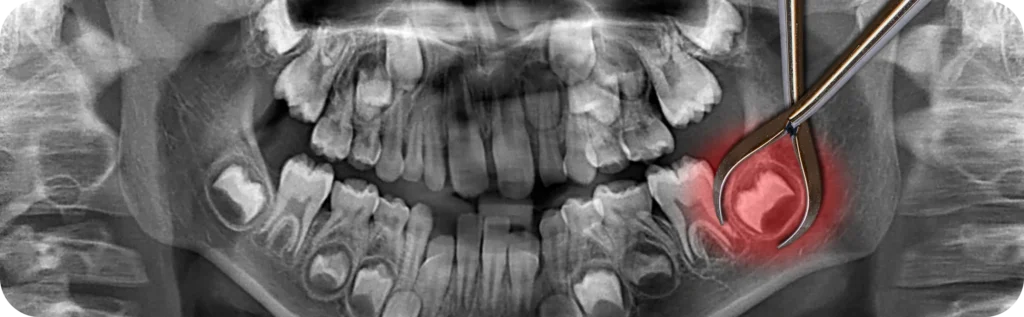

En premier lieu, un examen clinique complet est réalisé. Ensuite, une radiographie panoramique s’impose. En effet, elle permet de visualiser la position exacte des dents et leur proximité avec les structures nerveuses.

• Les différentes étapes de l’acte chirurgical

Dans certains cas, le nerf alvéolaire inférieur peut être touché. Cela provoque une perte de sensibilité du menton ou de la lèvre inférieure. Cette perte est généralement temporaire, mais un suivi s’impose.